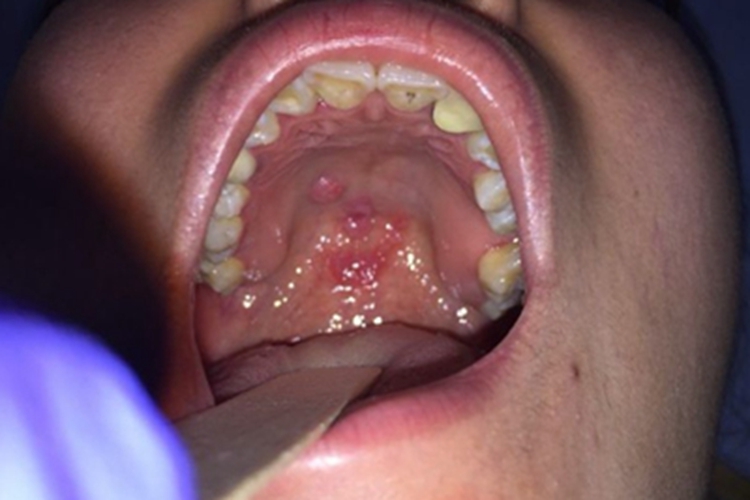

二期口腔梅毒的损害可发生于上牙膛,临床上可表现为初期黏膜充血,弥漫性潮红,无明显疼痛感,随病情进展,会逐渐形成类圆形的灰白色斑块,严重时还会出现浅表溃疡。

患者的一期口腔梅毒未经治疗或治疗不彻底导致病症加重,或者其他部位的梅毒螺旋体大量繁殖,由淋巴系统进入血液循环形成菌血症,并播散至全身,从而引起口腔黏膜损害,使上牙膛血管异常扩张,局部血液过多,出现充血症状。